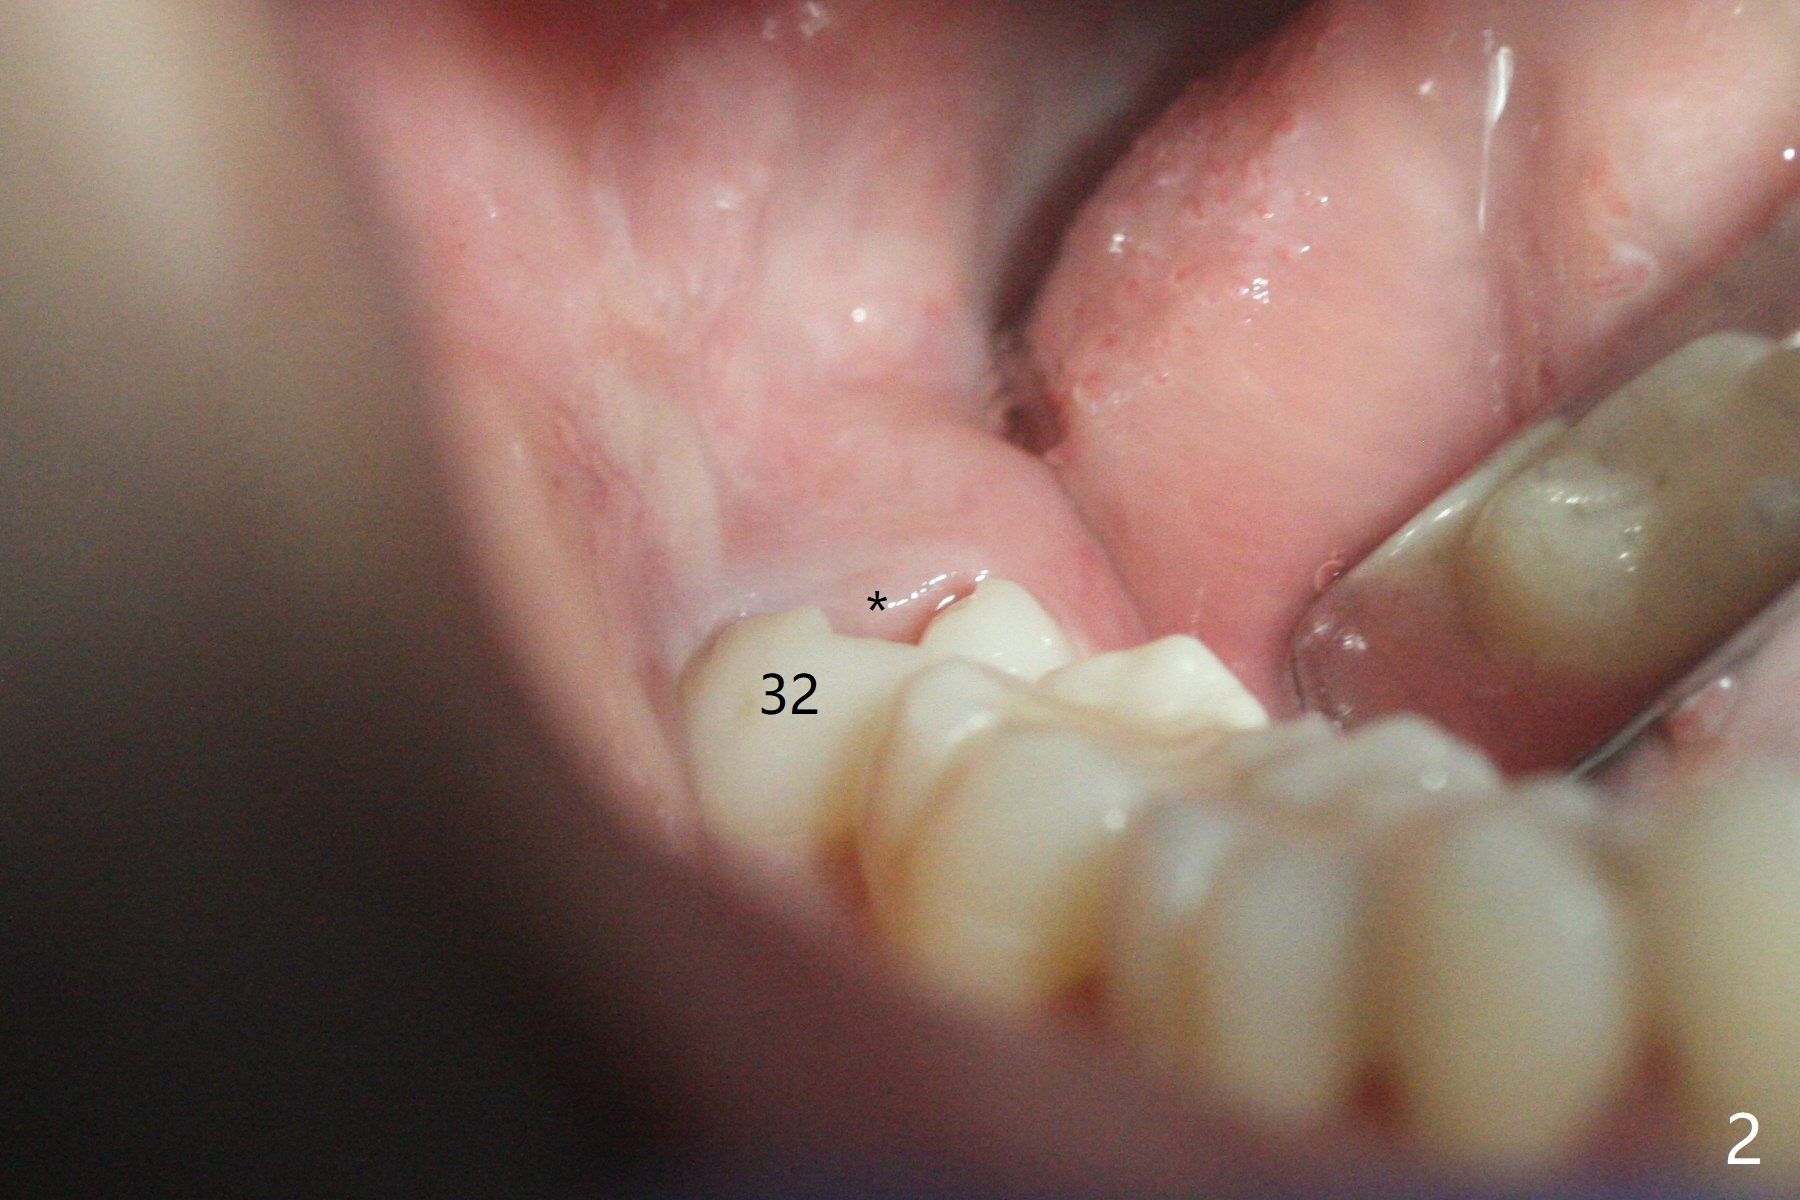

19岁女抱怨右下智齿远中龈下食物坎塞,不希望拔除,因为缺牙太多:先天性缺失一个下切牙,为了矫正又拔除4个双尖牙(图一)。临床检查32号牙远中牙龈覆盖(图二:*),而17号牙萌出不多(图三),没有食物坎塞史。局麻下,使用Diode Laser (Picasso)切除牙龈直到智齿远中咬合面暴露(图四)。术后突然意识到为了防止牙龈重新覆盖,必须做crown lengthening,也就是切除远中骨质(图五(黑色),与图一’对比),是吗?随访时利用Shining口扫记录,拍摄角度好。